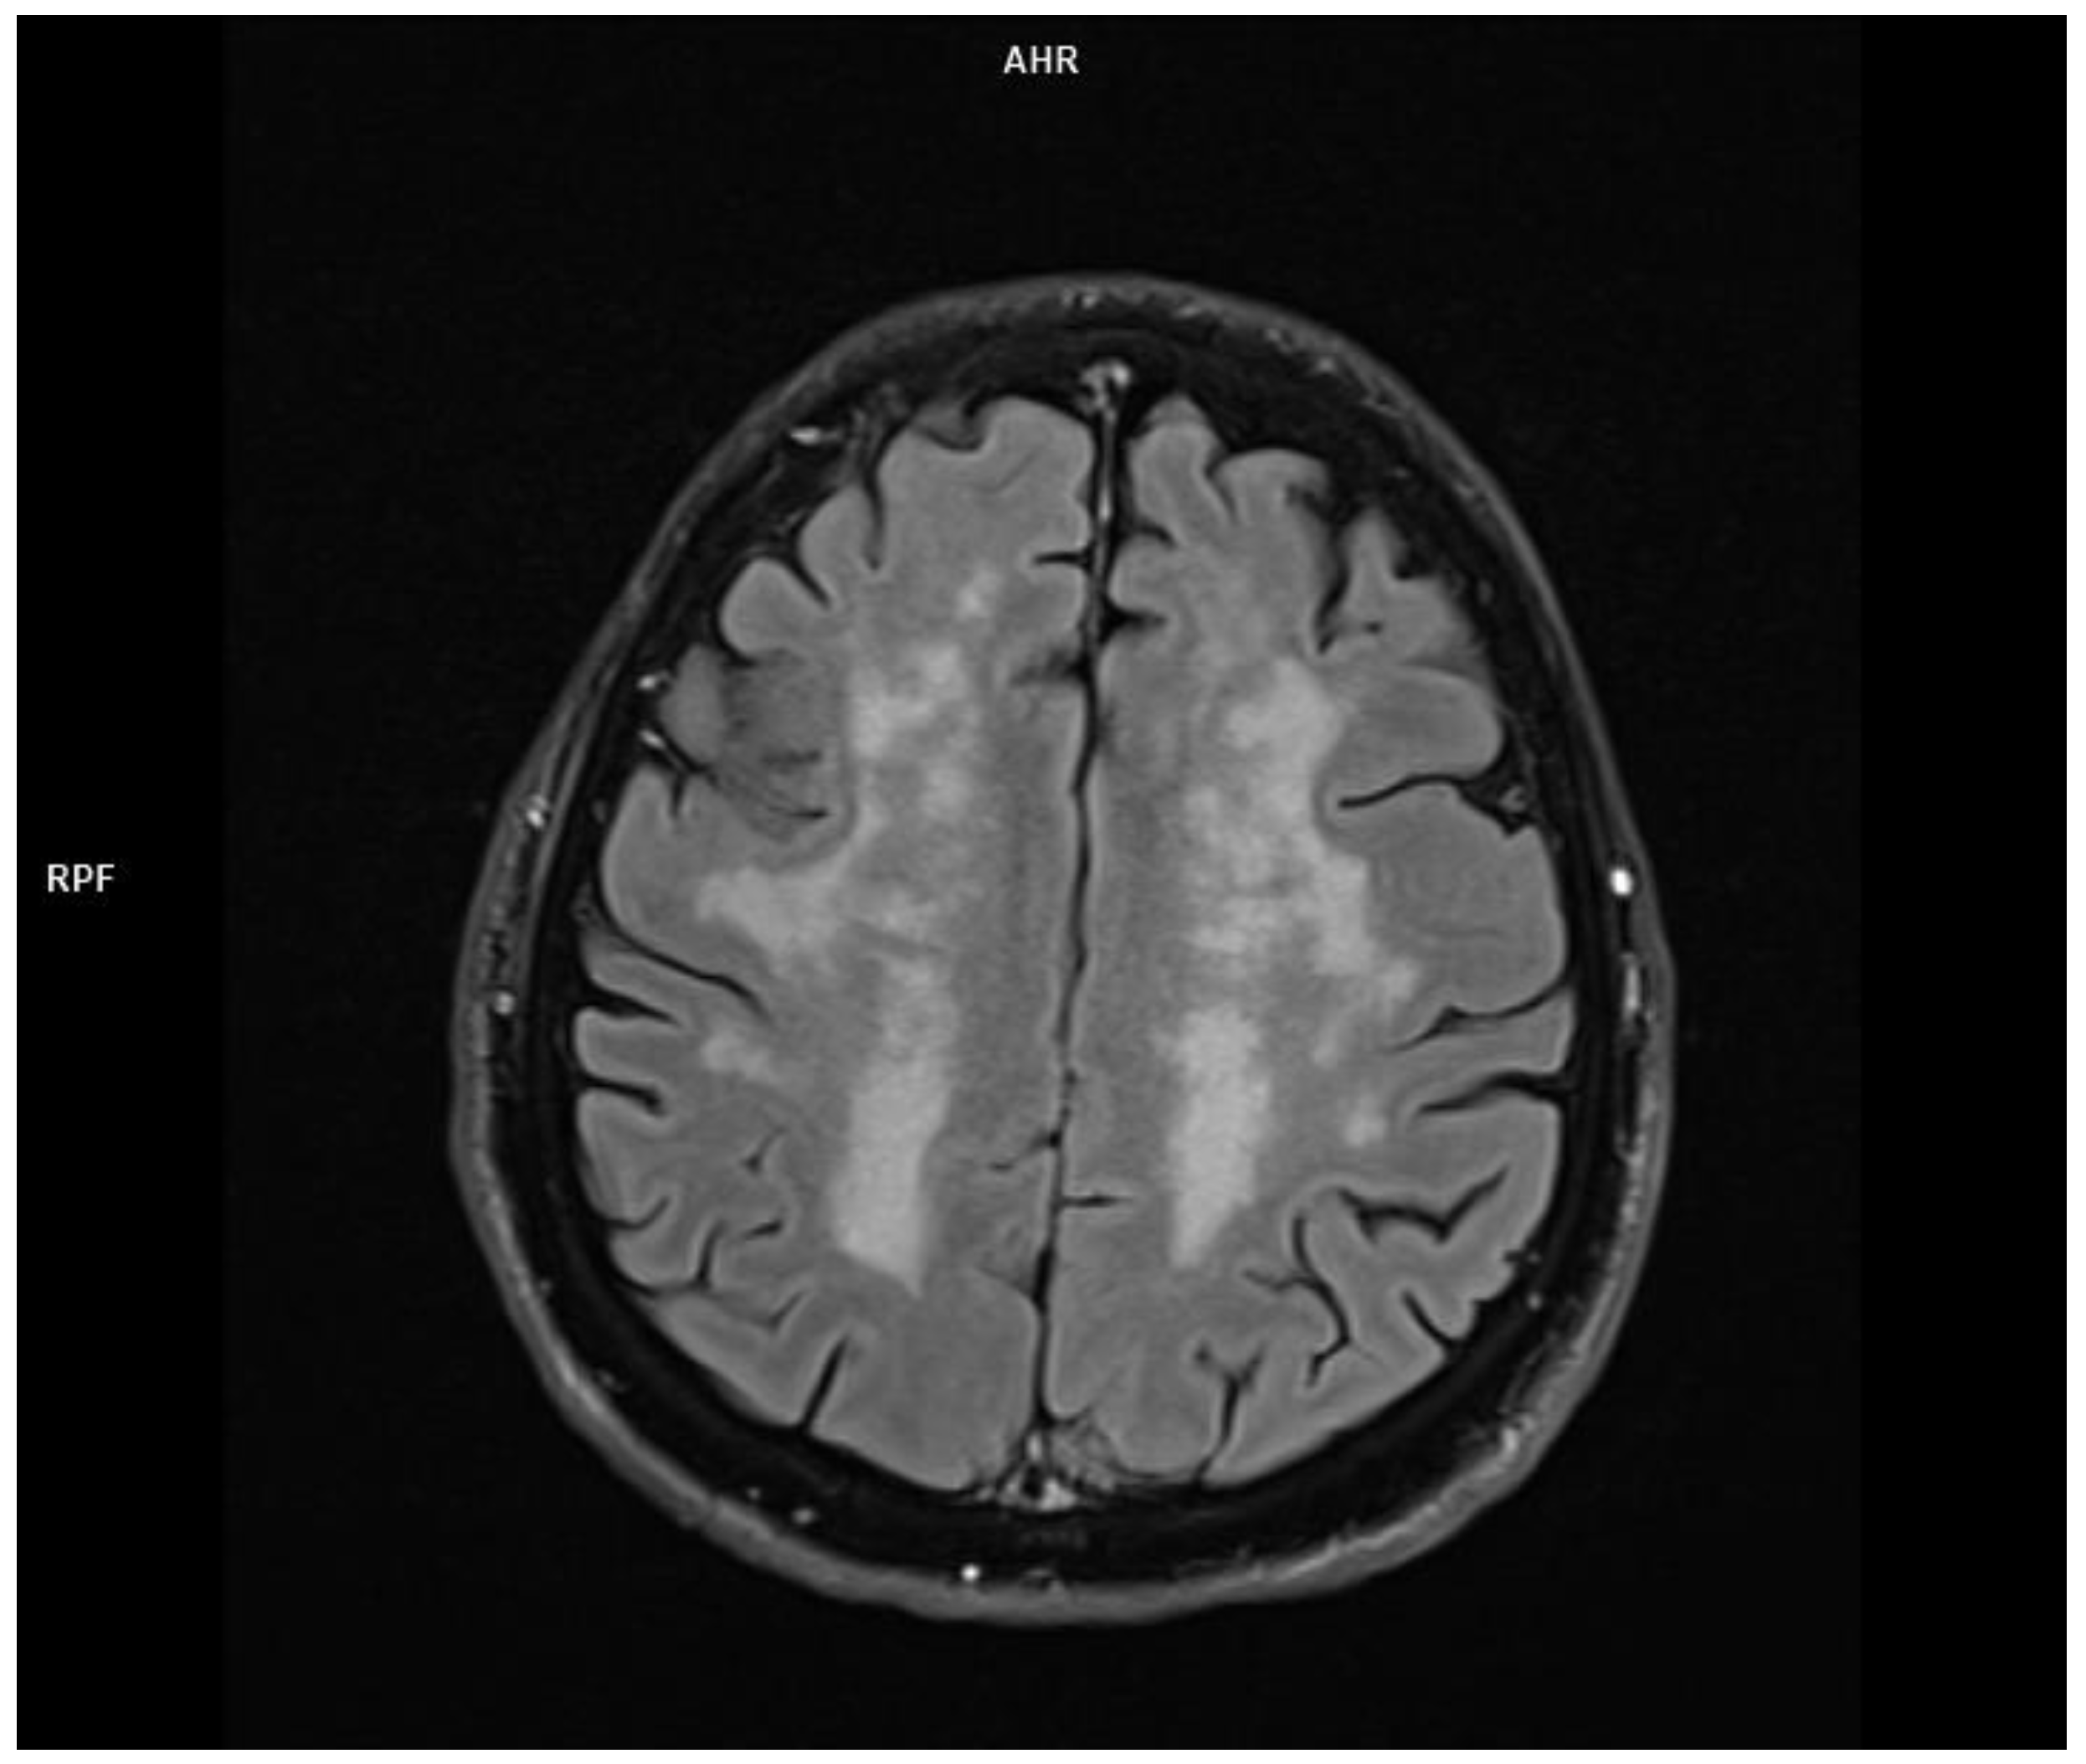

2.3. Patient 3